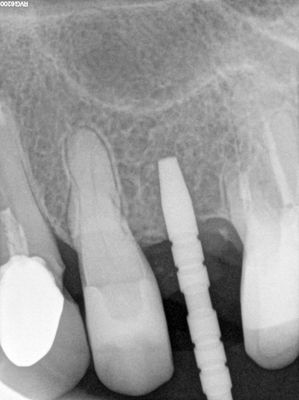

NSankhyan - immediate 13, impls 1121 and 25 with grafting

13 exo, loss of labial plate, implant placed buccal region grafted with sticky bone and collagen membrane soaked in prf fluid. 11/21 limited Labial-palatal width of bone, ridge split to 5mm, osteotomies prepared to about 2mm, remainder with densah drills, implants placed with ample bone, buccal grafted with same sticky bone. densah drills used for apical portion of 25 implant, soft bone, implant placed